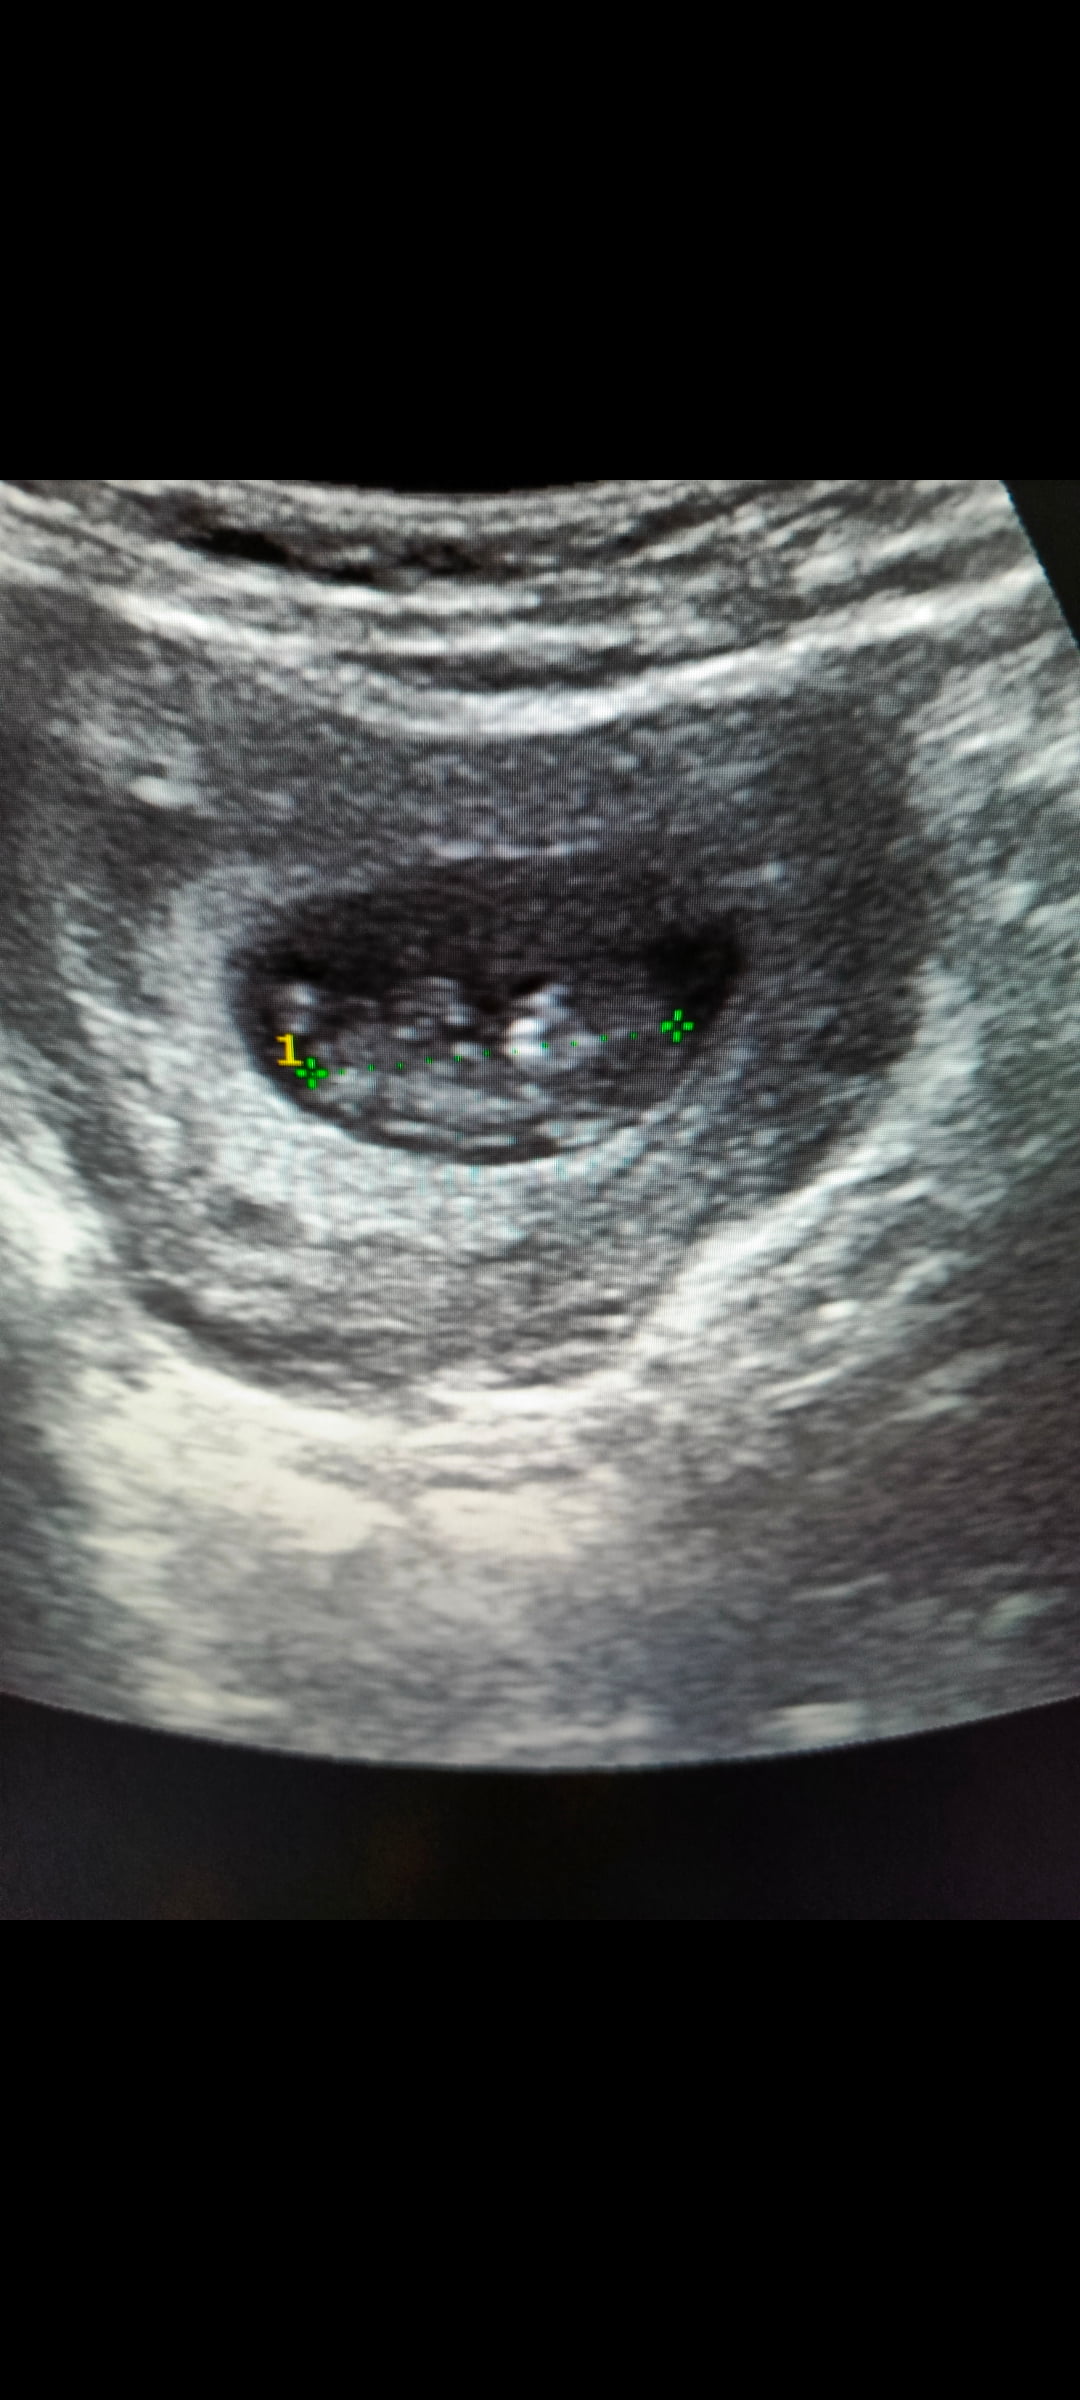

Bunada cinsiyet tahminin de bulunur musunuz

Banada cinsiyet tahmini yaparmisin

Kız bebiş kesesi gibi ![]()

Erkek bebiş kesesi gibi

Erkek bebiş kesesi gibi ![]()